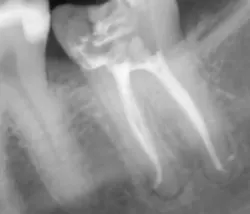

Once all of the canals are found, I will go through the series of Sybron Twisted Files size 25 tapering from 0.10 to 0.80 to 0.60 to 0.40. The 0.40 file should reach the working length for most canals. On a large palatal or distal canal, the 0.60 TF will usually reach working length. After which, using the crown-down technique with the Brasseler EndoSequence rotary files, instrument each canal until files reach the working length. Once instrumentation is complete, take a P.A. with gutta-percha to confirm instrumentation to working length. I find it much easier to take working length films with gutta-percha rather than files (which may fall out, bend, or separate)

Calcified canals

When approaching a calcified canal or a canal that’s curved and narrow, the C-files become a very important instrument. Sometimes, if the curve is very significant, I won’t use rotary files at all.